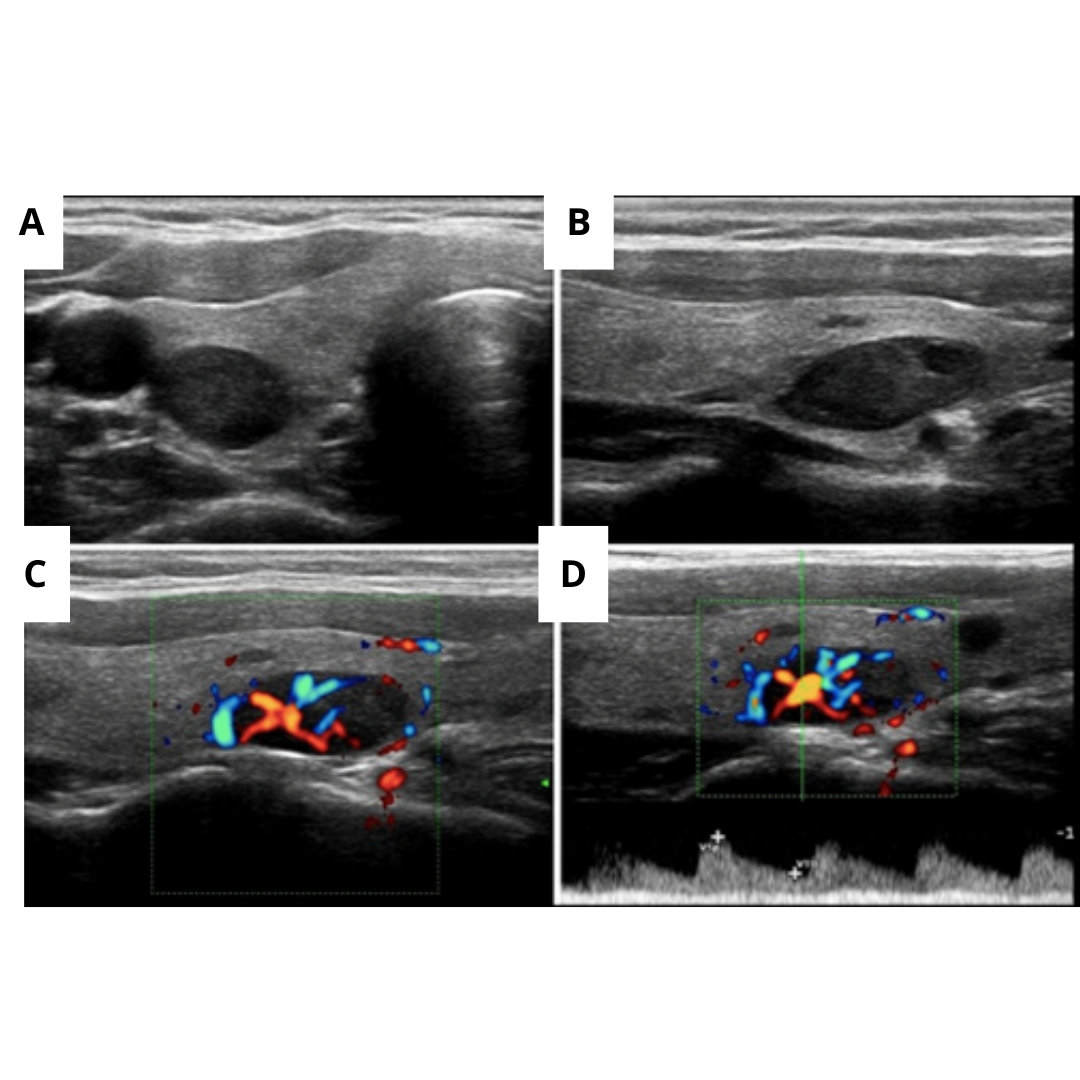

Figura 4: Adenoma infratiroideo de la glándula paratiroides

Paciente con imágenes nodulares en (A) transversal, (B) longitudinal, (C) longitudinal con Doppler color, y (D) Doppler espectral de la Arteria Aferente que reveló un flujo típico de baja resistencia.